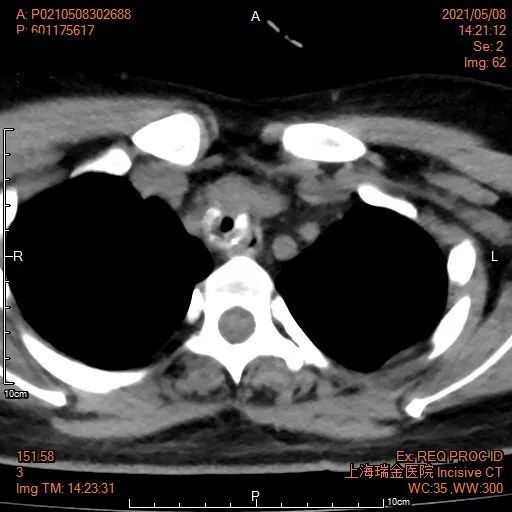

盈盈气管的CT

左图:盈盈凹陷的气管